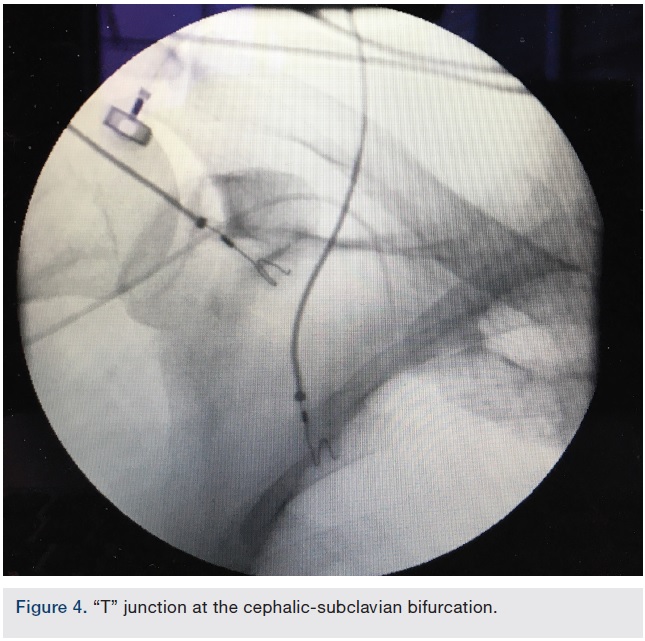

Balloon-tipped catheters suited for right heart catheterization are available in 5 to 8 French sizes. The majority of the prototypes have a thermodilution-capable version available. Usually a 5 French system is sufficient to obtain basic hemodynamic data. After placement of a hydrophilic introducer sheath, a balloon-tipped catheter is advanced through the upper extremity vein blindly without a guidewire. A gentle forward fluid flush may be used while advancing the catheter. If no resistance is felt while advancing, the catheter is advanced 30-40 cm without fluoroscopic guidance. At that point, the catheter tip is usually in the shoulder area, and fluoroscopy should be performed to further advance the catheter. If the catheter has travelled through the cephalic vein or its tributaries, it will encounter a “T” junction at the cephalic-subclavian bifurcation (Figure 4). Usually, a gentle forward push using fluoroscopic guidance is sufficient to enter the subclavian vein, which is a large caliber vein, and hence it is safe to inflate the balloon at this point, with further forward navigation, which may be performed with or without fluoroscopy, if the catheter passes through the desired path.